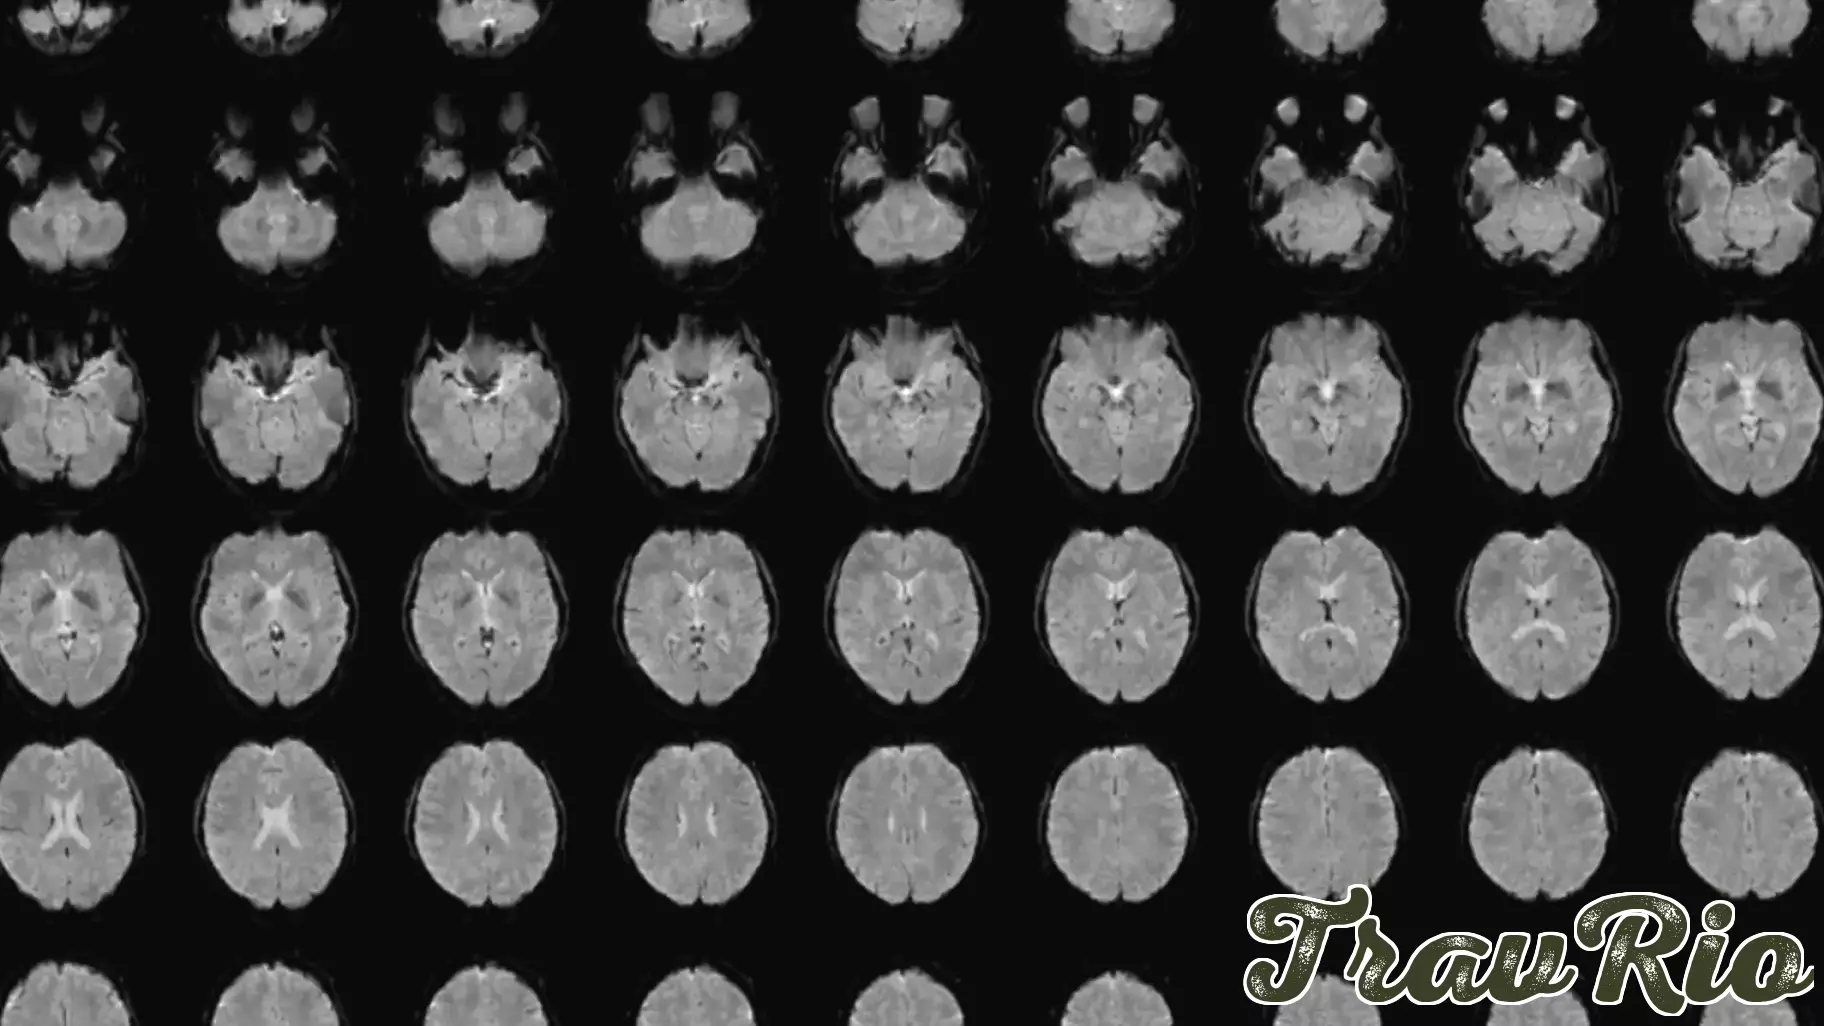

A groundbreaking technique has emerged from Japan, enabling the translation of mental images into coherent text through advanced brain scans and artificial intelligence. This innovative method, developed by scientist Tomoyasu Horikawa, marks a significant step forward in understanding how our brains process and articulate complex visuals.

While previous advancements have focused on converting thoughts into words, the challenge of transforming intricate mental images into descriptive sentences has remained largely unsolved. Horikawa's research, published on November 5 in the journal Science Advances, showcases the potential of this technology to bridge the gap between human cognition and digital communication.

By analyzing brain activity, the technique captures the essence of what individuals visualize and translates it into accurate language. This development not only highlights the capabilities of modern neuroscience but also opens new avenues for applications in fields such as psychology, communication, and even creative arts. The implications of this research could redefine how we express and share our inner thoughts and experiences.